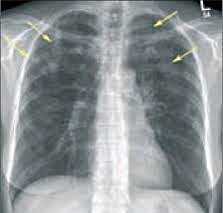

- Рентгенография легких. На снимках видны субплеврально расположенные одиночные (реже множественные, двусторонние) нечеткие затемнения средней интенсивности неправильной формы размером до 3-4 см. В окружении инфильтрата легочный рисунок усилен, тень корня легкого слегка расширена. Характерна быстрая динамика инфильтратов с миграцией по легочным полям и исчезновением не позднее 1-2 недель после обнаружения (чаще через 1-3 дня) без остаточной рубцовой деформации. При длительно поддерживающемся инфильтративном воспалении в ткани легких могут образоваться фиброзные очаги и кистозные полости.